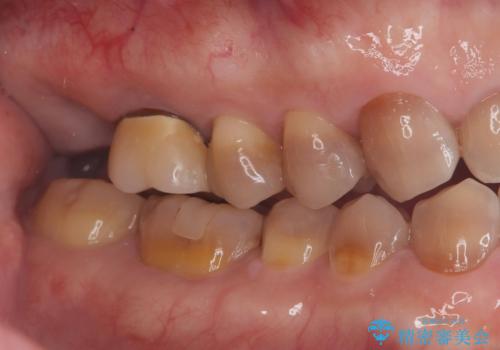

- 484,000円(インプラント手術と被せ物の費用全て込み)インプラント10年保障費用は治療当時の料金となります

抜歯と歯根嚢胞の除去を行った後、インプラントで治療しました。治療後は「自分の歯のように咬める」と大変ご満足いただけました。